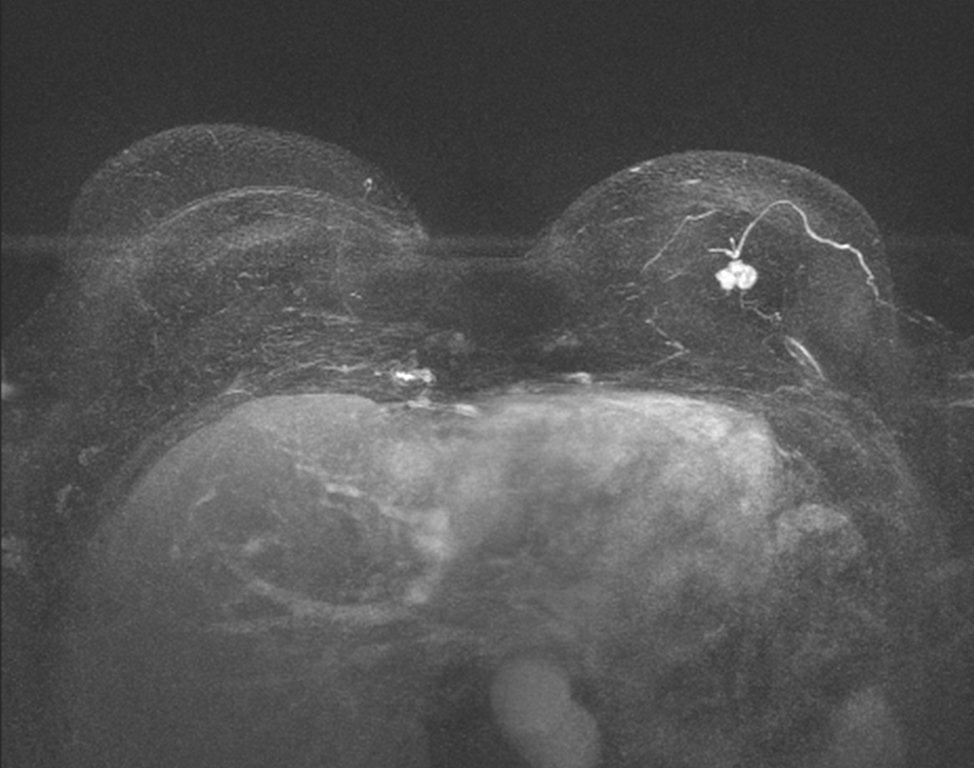

Mamma-MRT: Brusttumor Mamma-MRT: Brusttumor

Mamma-MRT: Brusttumor

(Zum Vergrößern bitte anklicken)